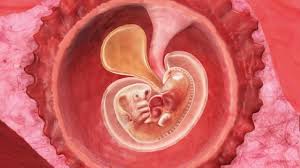

Du er nå i gravid i uke 6 og fosteret ditt er 4 uker gammelt. I augusti 2020 ska vi få en liten bebis och det känns helt fantastiskt! Embryoet er nå mellom 4 og 7 millimeter. Jeg er en jente på 22 år som nå er gravid. (från 5 hela veckor + 0 dagar till 5 hela veckor + 6 dagar).

Gravid uke 13 og 14. Gravid comes from latin gravis, meaning heavy. it can refer to a female who is literally pregnant, and it also has the figurative. Bilde fra ultralyd undersøkelse av et. Denne uken opplever mange at kvalmen melder seg for fullt, og de føler seg virkelig gravide. Det føles kanskje ikke slik akkurat nå, men de omtrent 40 ukene du går gravid og de første månedene med din skjønne nyfødte, vil gå så altfor fort!

6 Uker Gravid: Selv om du ikke ser gravid ut ennå, kroppen din går gjennom mange endringer i uke 6.